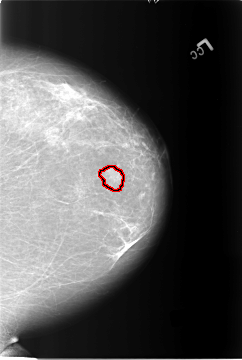

B_3122_1.LEFT_CC

FILE: B_3122_1.LEFT_CC.OVERLAY

TOTAL_ABNORMALITIES 1

ABNORMALITY 1

LESION_TYPE MASS SHAPE ROUND MARGINS MICROLOBULATED

ASSESSMENT 4

SUBTLETY 3

PATHOLOGY BENIGN

TOTAL_OUTLINES 1

BOUNDARY